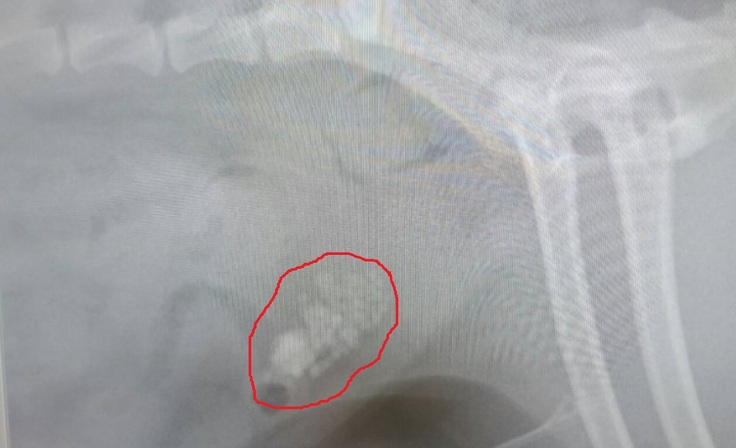

また、膀胱にも石が大量に増えていることも同時に発覚。

※以下レントゲン画像